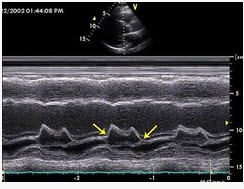

二尖瓣M型超声心动图,图中尖头所示两点称为()

A . E点和A点

B . D点和C点

C . F点和G点

D . 高点和底点

E . 前点和后点

[单选题]二尖瓣M型超声心动图,图中箭头所示两点称为()。A . E点和A点B . D点和C点C . F点和G点D . 高点和底点E . 前点和后点